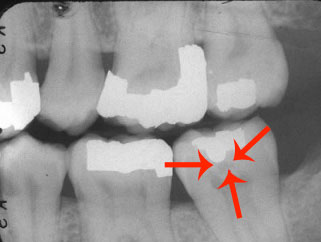

Pit and Fissure Caries (Figure 2). Includes Class I occlusal surfaces of posterior teeth, lingual pits of maxillary incisors, buccal surfaces of mandibular molars.

Figure 2. Pit and fissure caries.

Figure 2